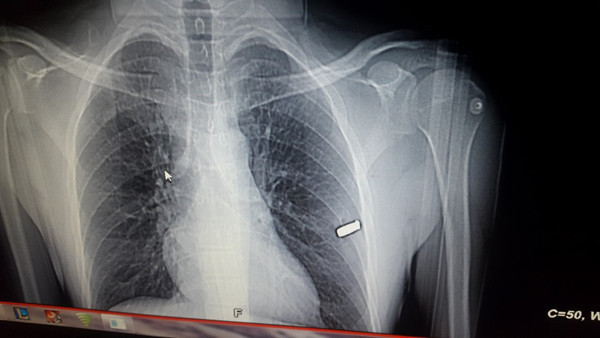

Muammer Uzun’un (47), taksicilik yaptığı İstanbul’da, FETÖ'nün 15 Temmuz darbe girişimi sırasında Çengelköy'de darbecilere karşı mücadele verirken açılan ateşle yaralandığı, 5 yıldır ise kaburgasına girip, hayati risk nedeniyle çıkarılamayan mermiyle yaşadığı ortaya çıktı.